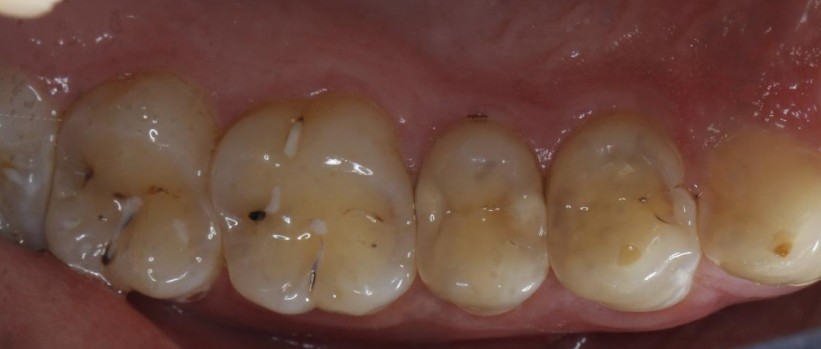

门诊经常遇到常年把碳酸饮料当水喝的患者,严重损伤了牙齿的健康,检查发现牙齿脱矿.龋坏特别严重,特别是邻面龋坏,治疗也非常麻烦,很多情况下,简单的补牙都解决不了长久性问题,想要经久耐用,可以选择嵌体,高嵌体,全瓷牙冠修复,更重要是杜绝不良嗜好;有图有真相!我们采用德国西诺德瓷睿刻即刻修复系统,等待1小时,完成当日修复。